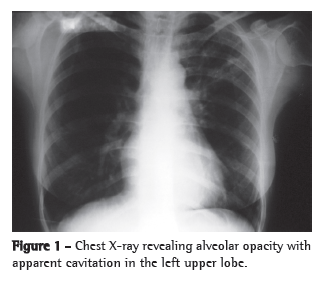

Clinical caseWe report the case of a 41-year-old female homemaker from the city of Piracanjuba, located in the state of Goiás, Brazil. The patient had previously been diagnosed with arterial hypertension and had been using enalapril for several years. In addition, she had been diagnosed with RA more than ten years prior. During that period, she was treated with various therapeutic regimens for RA. She had been under treatment prednisone (5 mg/day) and methotrexate. Since she continued to have many joint symptoms, adalimumab was also prescribed. After two months of adalimumab treatment, the patient began to have low fever almost daily, as well as mild dry cough and mild asthenia. She sought medical attention at an emergency room in the city of Goiânia, also located in the state of Goiás, and was diagnosed with pneumonia after a chest X-ray (Figure 1). The patient used azithromycin (500 mg) for five days, in accordance with a prescription. The patient initially presented a slight improvement, but the dry cough and fever returned after the medication was discontinued. Two months later, since her clinical profile remained the same, she sought medical attention again, at which point a ten-day course of levofloxacin (500 mg/day) was prescribed. Again, she presented a slight improvement but the symptoms reappeared after the end of the course.

The patient stated that she was not a smoker or an alcoholic. She reported that she had tested negative on a tuberculin skin test (TST) conducted before the initiation of adalimumab treatment, and that, according to the rheumatologist who treated her, a chest X-ray performed at the time was normal. After the use of azithromycin (three and half months prior), she also received an additional infusion of adalimumab. Physical examination revealed mild pallor and no palpable lymph node enlargement. There were fine rales in the upper third of the left hemithorax and coarse rales in the middle third of the right hemithorax, as well as scattered rhonchi. Her hands and feet had joint deformities. A chest X-ray revealed alveolar opacities in the left upper lobe, left lower lobe and middle lobe, as well as images suggestive of bronchogenic dissemination (Figure 2). A CT scan of the chest revealed tree-in-bud centrilobular opacities (Figure 3).